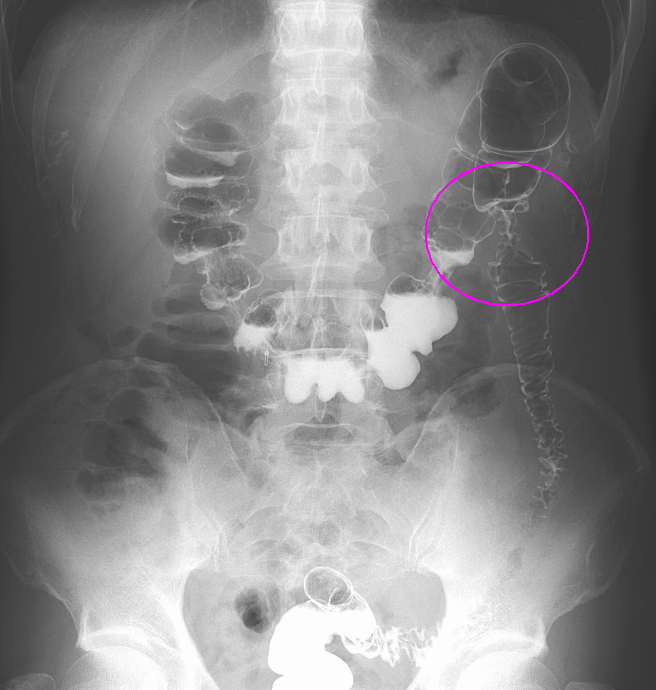

閉塞性大腸がんに対する大腸ステント治療

大腸がんが進行し腸が詰まってしまう閉塞性大腸がん(大腸がん腸閉塞)に対する治療です。従来は人工肛門を造設して対処していましたが、人工肛門はケアの負担やにおいに対する不安などからQOL(生活の質)低下が避けられません。そのため当院ではステントと言われるメッシュ構造の金属製の網を用いて詰まりを解消し、人工肛門を回避する治療を行っています。大腸ステント治療は緩和治療を目的に行う場合と根治手術前に全身状態の回復を目的として行う場合があります。

治療前

ステント留置後(内視鏡画像)

ステント留置後(レントゲン画像)